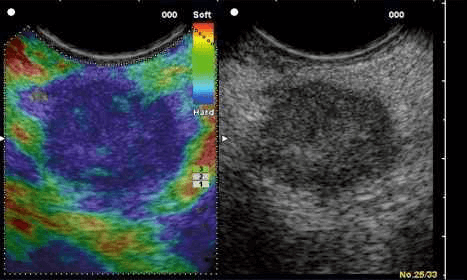

Strain Elastography (left) vs Shear Wave Elastography (right)

Stress is applied by repeated manual compression of the ultrasound transducer. The amount of lesion deformation relative to the surrounding normal tissue is displayed as a color-coded image. It primarily helps characterize superficial structures as in thyroid, breast and the uterine cervix. A strain map helps visually interpret, with respect to a reference color bar, if the lesion is soft or hard relative to the surrounding tissue.

A real-time color-coded strain map (left) of the B-Mode ultrasound image (right). In this image, the tissue in blue is of hard and tissue in red is of soft consistency with the yellow-green shades representing soft-to- firm consistency, as indicated by the reference color bar to the top right of the strain image.

Strain Elastography of a firm to hard breast lesion: a fibroadenoma

Strain Elastography of a breast cyst – soft in consistency, as indicated by red on the strain map.